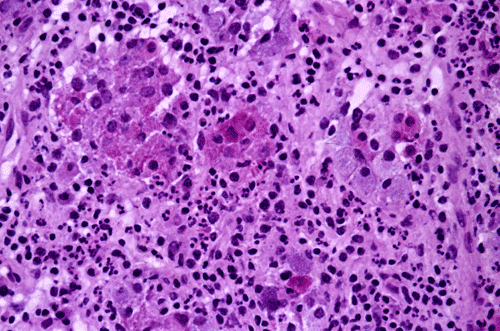

Findings on the permenant sections are not that much different from  the frozen sections. There is widespread lymphocytic infiltration in anterior pituitary tissue. Residual islands of anterior pituitary cells in form of pink clusters of cells at this magnification can be well recognized (Panel D). Residual anterior pituitary cells with amphophilic cytoplasm (chromophobes) and eosinophilic cytoplasm (acidophils) are present. There are also scant eosinophils. No cellular atypia is noted in either the inflammatory component or epithelial component (Panel D and E).

The histopathology of lymphocytic hypophysitis is well illustrated in this case. In essence, there is a lymphoplasmacytic infiltrate in a background of adenohypophysial tissue. There is a variable number of neutrophils, eosinophils, and histiocytes. Lymphoid aggregates are common features. The infiltrating lymphocytes are polyclonal in nature and can be well demonstrated by immunohistochemistry. This is a useful feature that distinguish lymphocytic hypophysitis from neoplastic lymphoproliferative disorders. A variable degree of fibrosis and atrophy of the adenohypophysial tissue tissue can be seen. The residual adenohypophysial epithelial cells may exist as small islands and may show oncocytic changes.